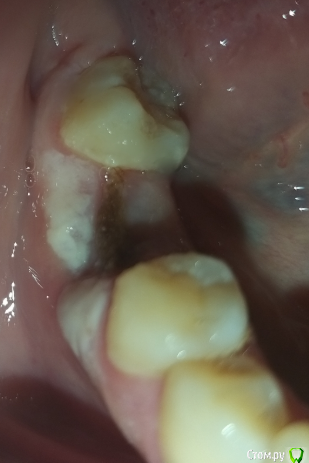

halsey Опубликовано 14 мая, 2020 Поделиться Опубликовано 14 мая, 2020 (изменено) Добрый день! Скажите, пожалуйста, удалила зуб 6-ку снизу (под коронкой, нервы удалены были давно) 3 недели назад,пилили на 3 части, вытаскивали по частям, под корнем была огромная киста... на форуме есть фото рентгена.. после удаления врач туда что-то вонючее положил )) пахло йодом, я видела какую-то жёлто-зелёную тряпочку..ни во время ни после удаления ничего не болело, ни выпила ни одной таблетки, температура не поднималась ни разу, сейчас ничего тоже не болит..но выглядит как-то странно, я ни разу не удаляла зубы. там сейчас на десне белый налёт, со стороны щеки,а в месте между 5ым и 7ым зубом что-то темное, какого-то темно-желто-зеленого цвета.. как будто десна слева, десна справа, а посередине вот это что-то... как будто полоска темная.я попыталась это потрогать языком.. вроде не твердое.. короче, что это )) может, это надо вытащить? я туда ничем не лазила.. ничего не трогала, это так и надо? оно само отвалится?... надеюсь, не самый глупый вопрос!) Изменено 14 мая, 2020 пользователем halsey Ссылка на комментарий

halsey Опубликовано 14 мая, 2020 Автор Поделиться Опубликовано 14 мая, 2020 по-моему это та коричневая штука, которую он мне в зуб и клал)) наверное, само отвалится ... Ссылка на комментарий

Irouil Опубликовано 14 мая, 2020 Поделиться Опубликовано 14 мая, 2020 нужно? боюсь даже и не попаду сейчас к немуНичего опасного для здоровья не вижу, но налёт действительно выглядит странно Ссылка на комментарий

halsey Опубликовано 15 мая, 2020 Автор Поделиться Опубликовано 15 мая, 2020 Ничего опасного для здоровья не вижу, но налёт действительно выглядит странносегодня налет пропал , как вы сказали, стала активно полоскать, а вот эта штука коричневая там.. )) Ссылка на комментарий